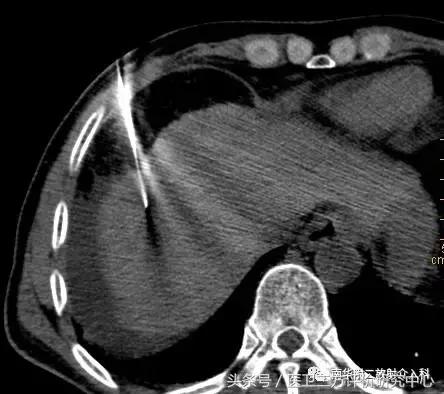

CT引导精准定位